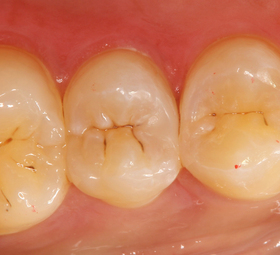

下の写真は隣接面の虫歯がある歯です。

穴が開いていないので、どの歯が虫歯になっているかわかりにくいと思いますが、

⇓で指し示した、すこし歯の色が変わっている部位が虫歯です。